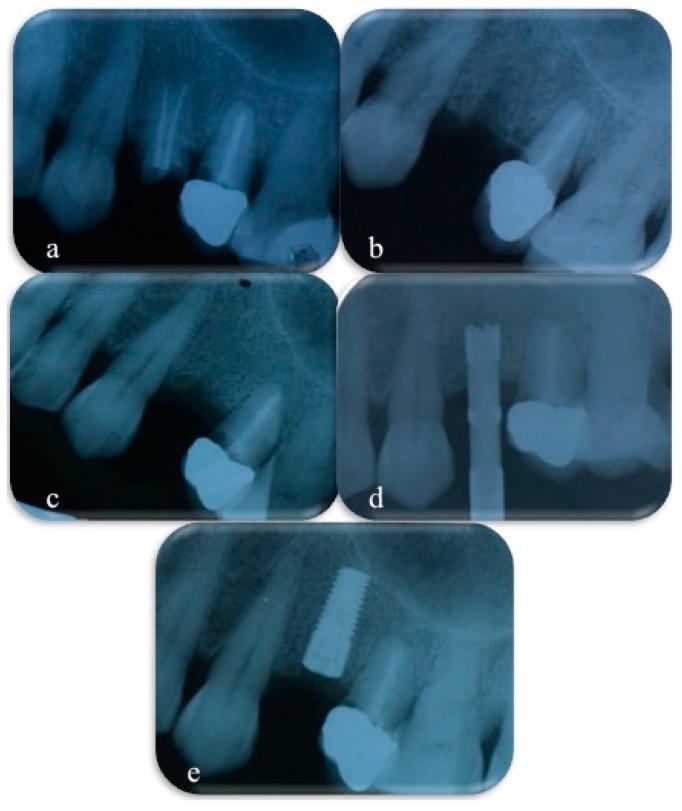

10 subjects were enrolled for single or multiple tooth extraction and implant placement. Each site was randomly assigned to one of four groups and filled with CS, NHA, a combination of CS and NHA, or left to normal healing. After five months tissue samples were harvested from the extraction sites and prepared for histological investigations.

招募10名受试者进行单颗或多颗牙齿拔除及种植体植入。每个部位随机分为四组之一,分别填充CS、NHA、CS与NHA的组合,或任其自然愈合。五个月后,从拔牙部位采集组织样本,准备进行组织学研究。